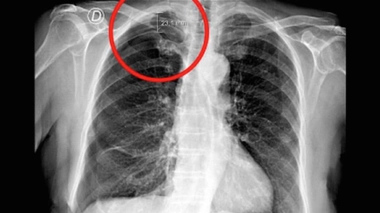

Une femme fait un pneumothorax à cause d’une séance d’acupuncture

Le pneumothorax est mis en évidence dans le cercle rouge. Il correspond à une poche d'air de 23 mm entre le poumon et la cage thoracique.